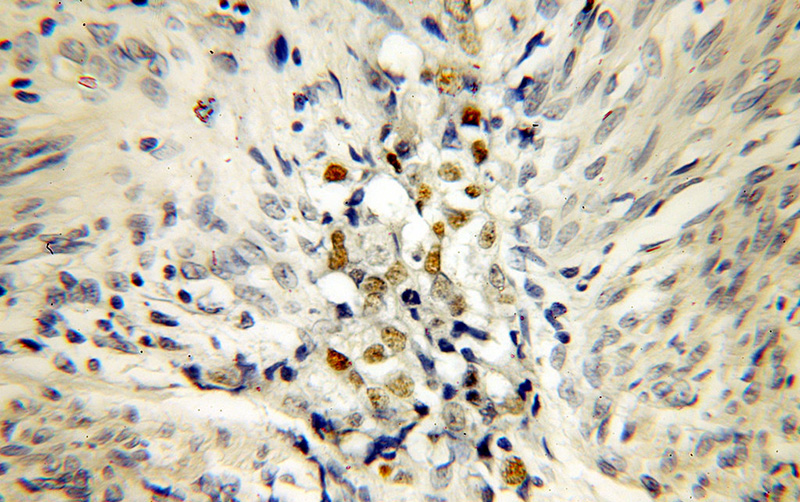

Immunohistochemical of paraffin-embedded human endometrial cancer using Catalog No:113553(P53 antibody) at dilution of 1:100 (under 10x lens)

Immunohistochemical of paraffin-embedded human endometrial cancer using Catalog No:113553(P53 antibody) at dilution of 1:100 (under 40x lens)